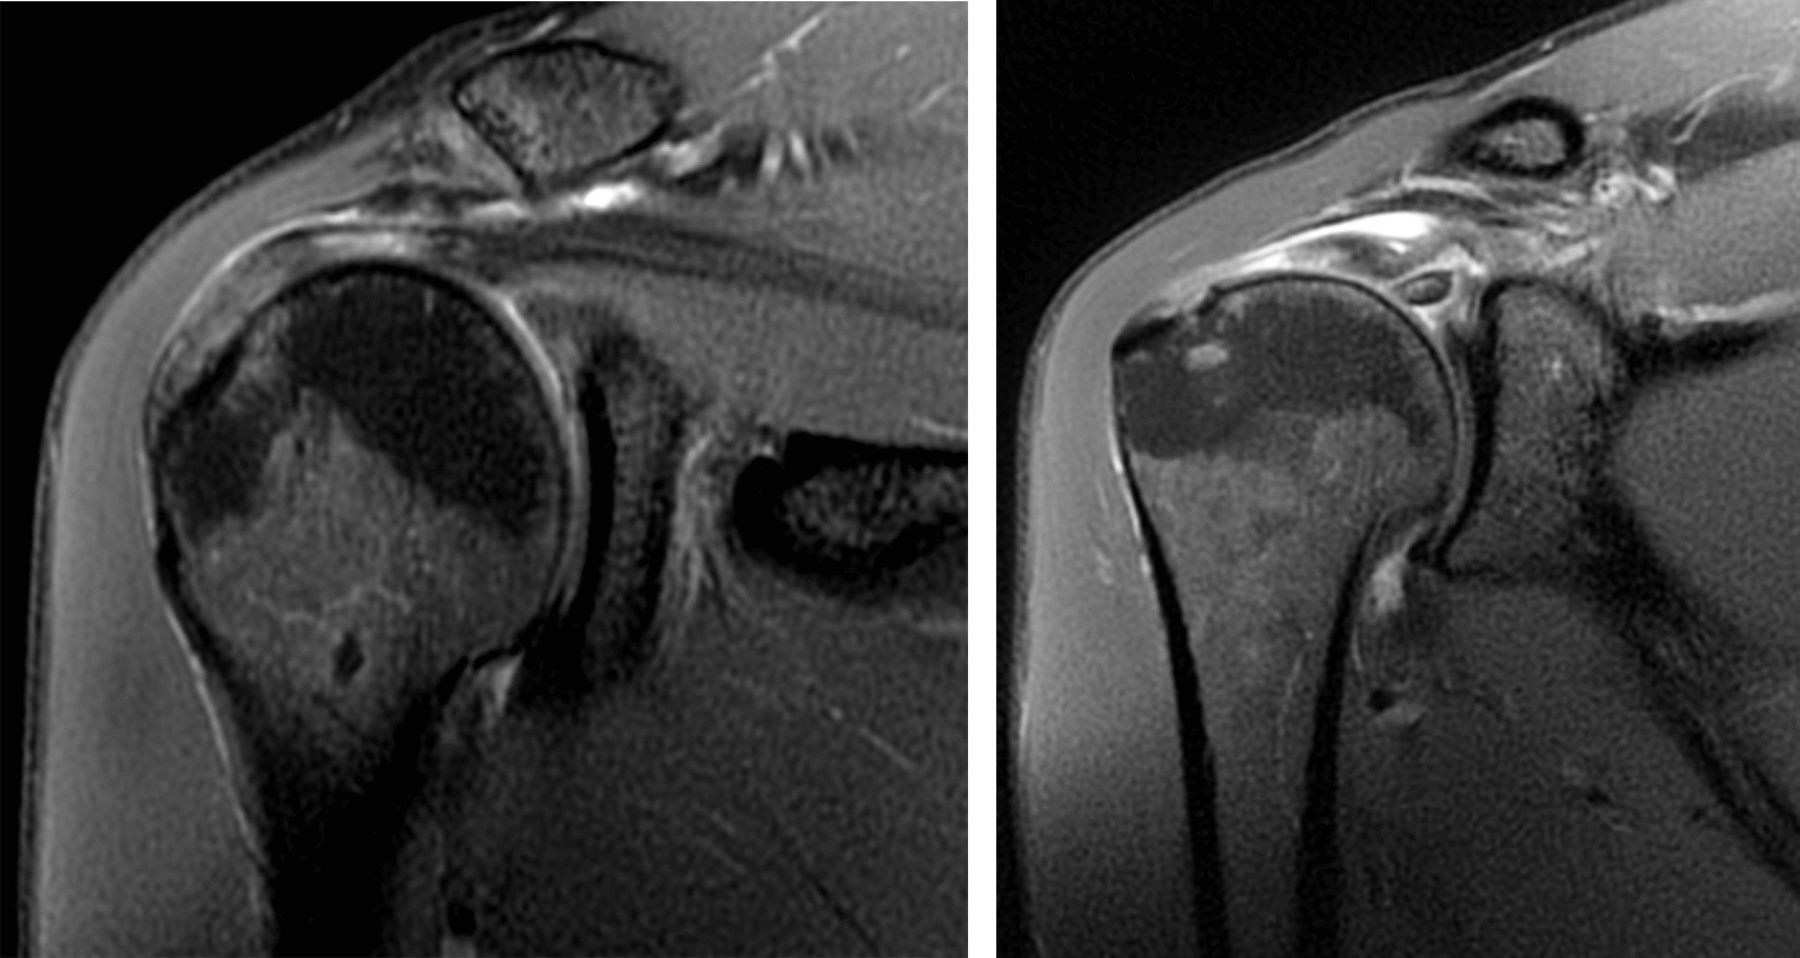

La resonancia magnética evidencia, como diagnóstico principal, una ruptura-avulsión completa de la porción larga del bíceps en su sitio de origen en el tubérculo supraglenoideo, con retracción distal de sus fibras (corredera bicipital vacía) (Figuras 1 y 2). Como hallazgo secundario, se observa tendinitis con ruptura parcial intrasustancia y de la unión miotendinosa del supraespinoso (Figura 3). Estos hallazgos explican de forma precisa la correlación clínica e imagenológica descrita en la solicitud, y demuestran la alta sensibilidad y especificidad de la resonancia magnética de hombro para la detección detallada de lesiones musculoesqueléticas.

Figura 3